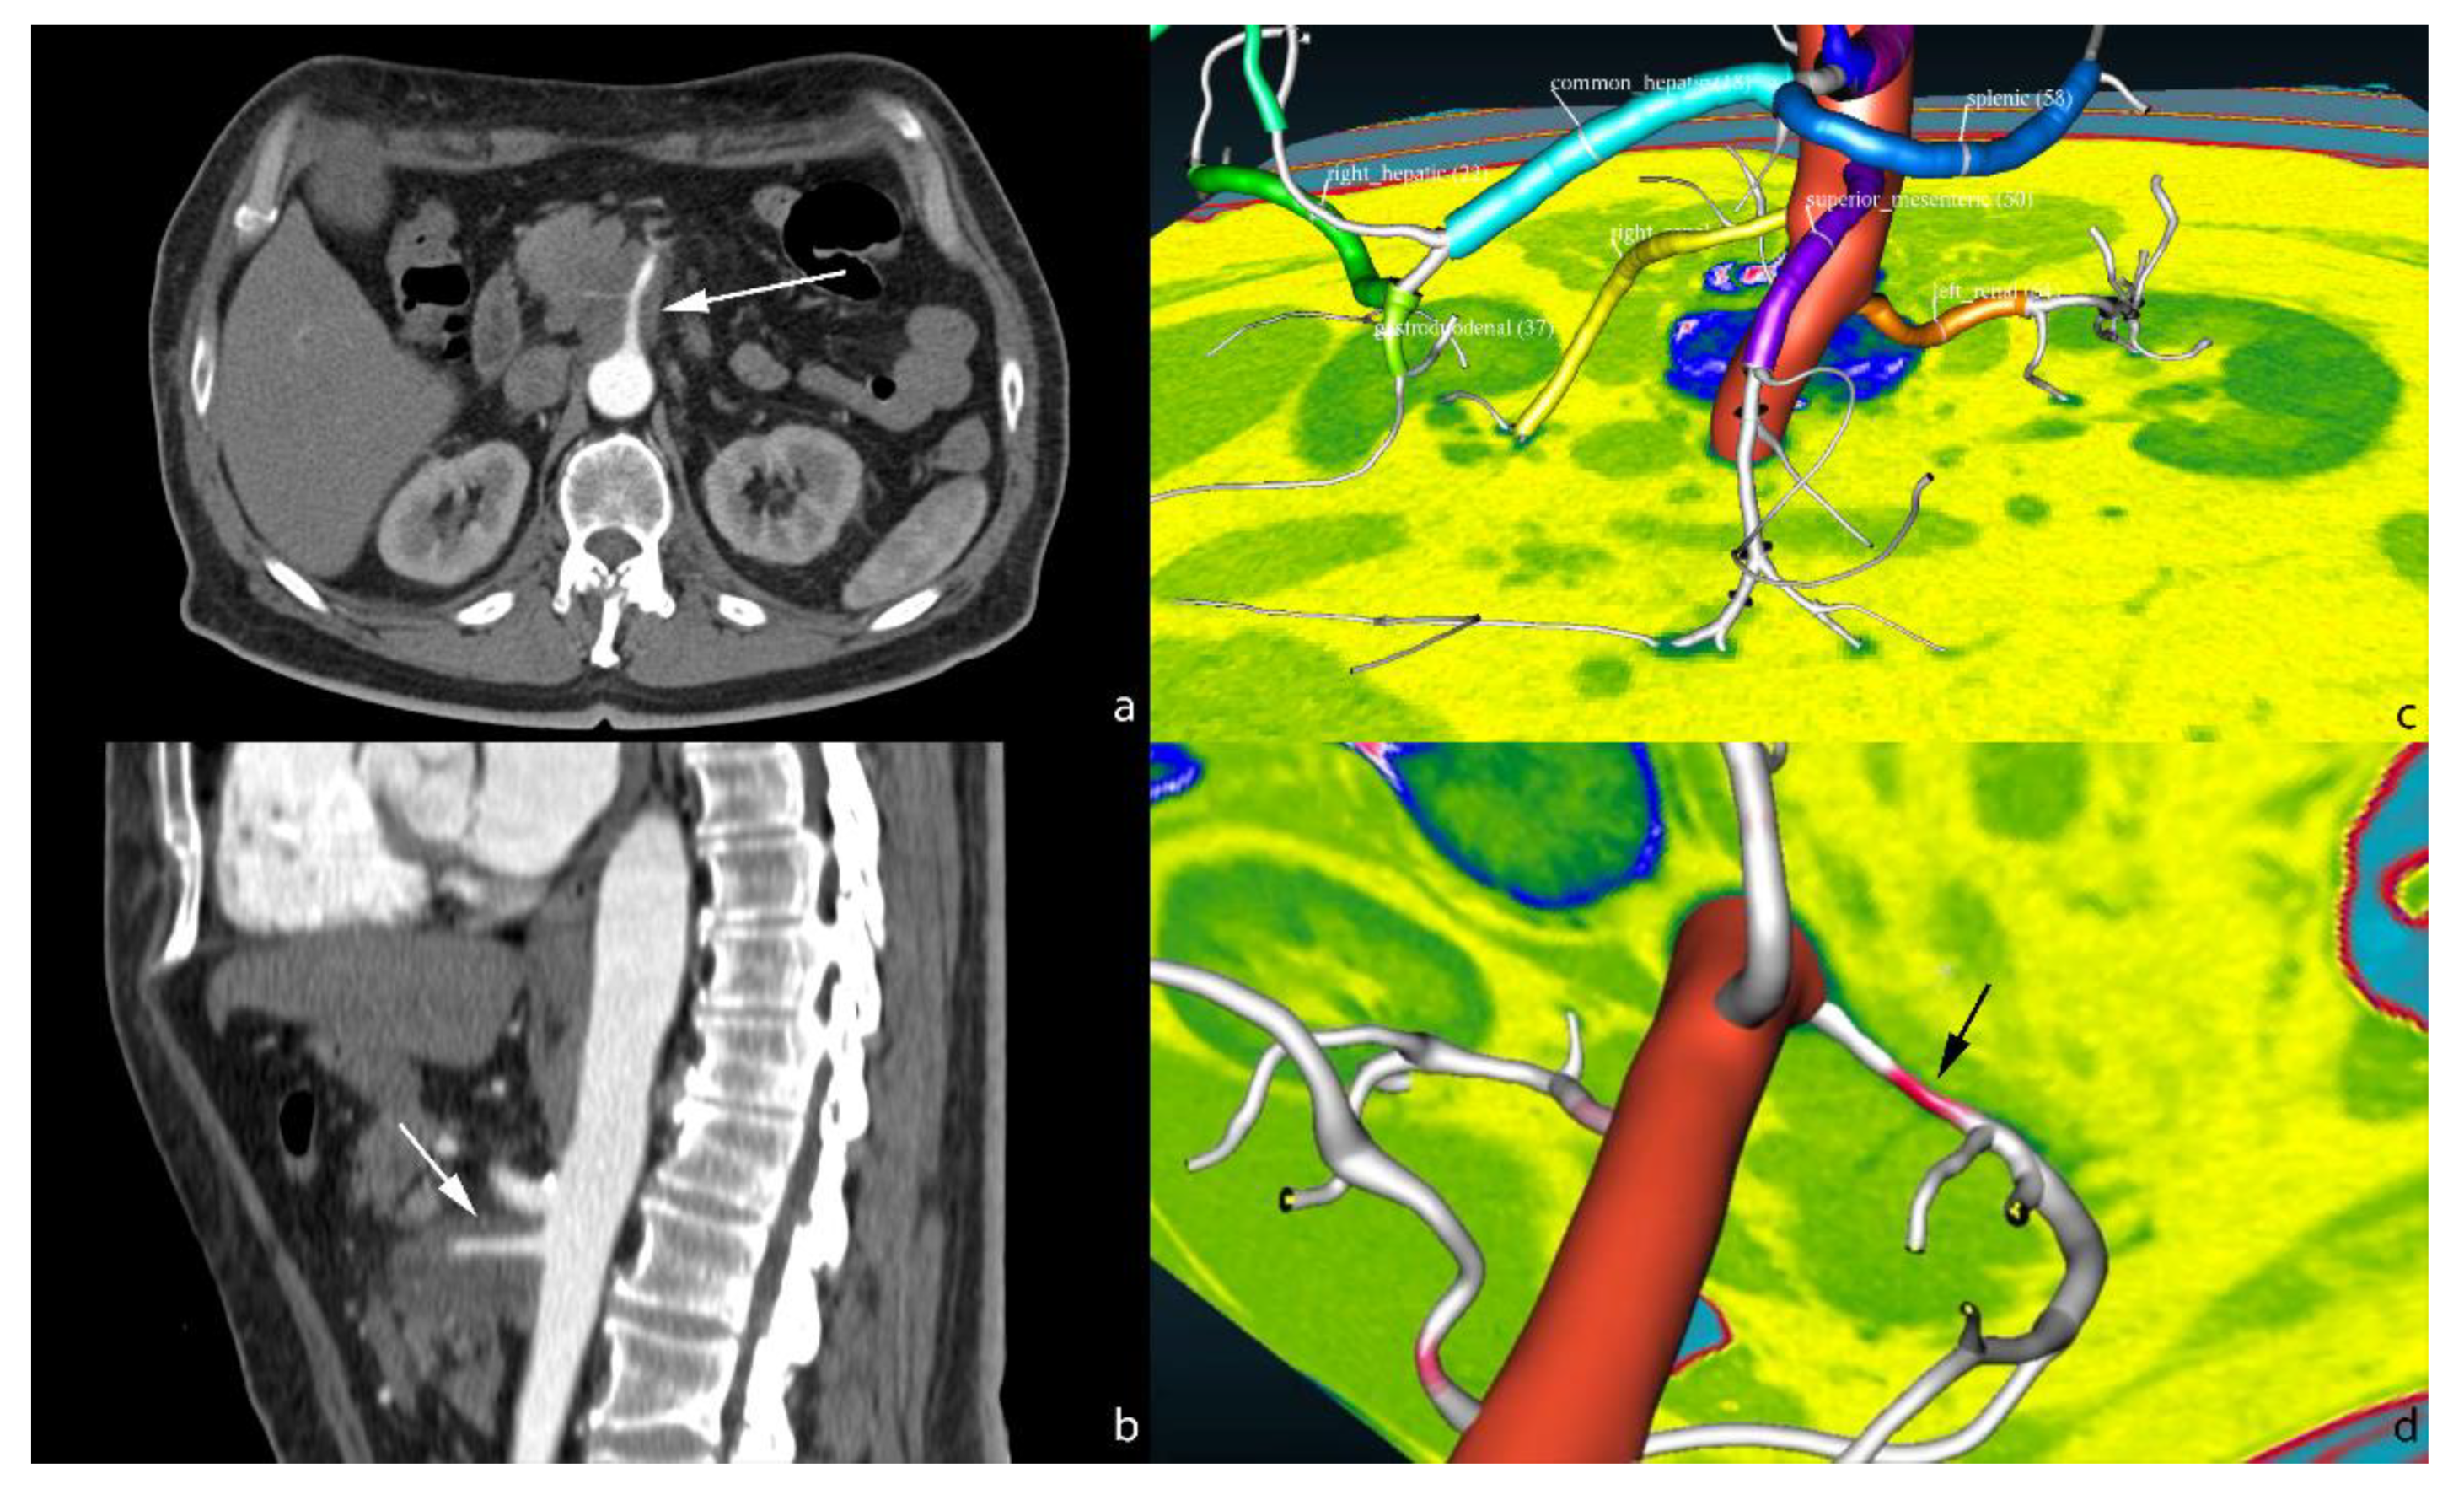

- Fabiano, F.; Dal, P. An asp approach for arteries classification in CT-scans? CEUR Workshop Proc. 2020, 2710, 312–326. [Google Scholar]